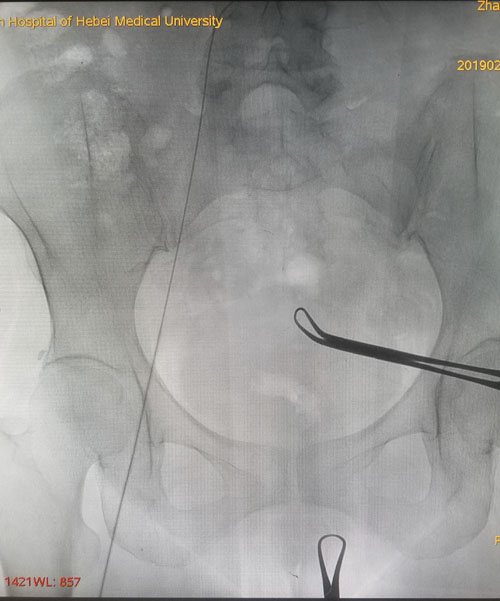

术中DSA评估导丝走形

术后DSA评估导管尖端位置